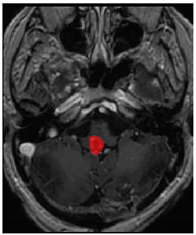

Three cases from the NTUH dataset showing representative results of different models were shown in Table 2, Table 3 and Table 4. The overall dice scores of these networks on the NTUH dataset ranged from 0.33 (DeepMedic) to 0.51 (V-Net). Table 5 shows the detailed performance of each network tested with the NTUH dataset.

On the NTUH datasets, the performance was also affected by the types of lesions. As shown in Figure 1, we obtained better results for brain metastases, meningiomas, and schwannomas, while all models performed poorly on pituitary tumors, AVMs, and other tumor types. Detailed tables are attached as Appendix A, Appendix B, Appendix C.

Ground truthDeconvNetDeepMedic

Applsci 11 09180 i001 Applsci 11 09180 i002 Applsci 11 09180 i003

PSPNetU-NetV-Net

Applsci 11 09180 i004 Applsci 11 09180 i005 Applsci 11 09180 i006